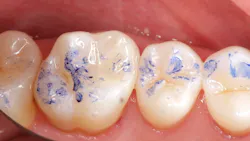

While performing esthetic dentistry, our bonding materials must work as promised to achieve long-term success.2 When manufacturers report bond strengths in the clinical arena, studies are conducted with the rubber dam in place (figures 1 and 2). When etched surfaces are exposed to the oral environment, including expired air while using typical isolation devices, the surfaces are challenged by moisture from numerous sources, causing the adhesive chemistry to be altered. Hence, to achieve the best bond strengths, a well-sealed barrier will help our results, often dramatically.